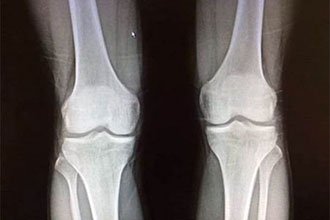

美国纽约大学医学和牙科学院的一个多学科综合治疗小组,已经研发出了一种能够促进骨骼生长的3D打印植入物。 研究人员在《组织工程学和再生医学》杂志上发表的论文称,这种植入物的功能是充当生物活性支架。首先类凝胶贝塔磷酸三钙被打印成酷似医生需要修复的骨骼形状。这种凝胶中含有与真正骨骼中相似的化合物,通过过热作用凝胶就会形成一种陶瓷植入物。

一旦植入到人体中,这种陶瓷支架会充当真正骨骼生长的一种模板。它们的化学构成也意味着它们会随着时间的变化被吸收,逐渐分解而且只留下新的骨骼。患者自身骨骼快速生长的关键之一就是在植入物表面覆盖了一层双嘧达莫。其它实验进行的测试表明,这种做法能够让骨骼生长速度加快50%。双嘧达莫也会吸引骨骼干细胞,从而刺激新生骨骼内供养血管和骨髓的生长。据研究人员称,借助这种凝胶支架生长的骨骼将和自然生长的骨骼一样具有柔韧性。